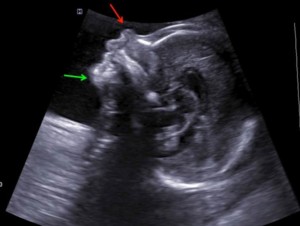

این تصویر نمونه ای از بررسی جنین در هفته 21 بارداری است. می توانید به راحتی پیشانی، بینی (فلش قرمز)، لب ها و چانه (فلش سبز)، پس گردن و بخشی از قفسه سینه را شناسایی کنید.